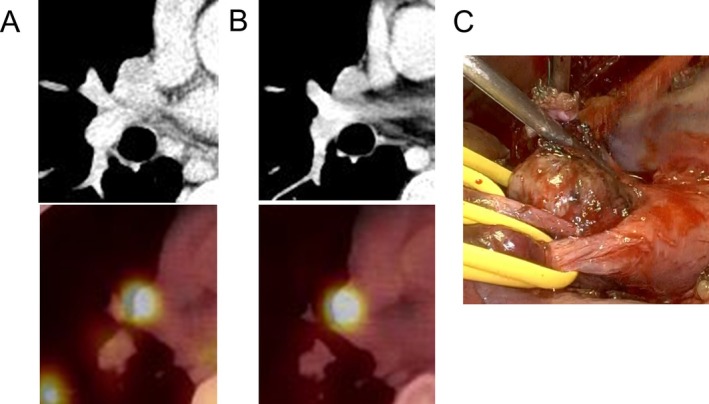

Extra-adrenal paraganglioma is a rare tumor and is difficult to diagnose. We report a case of extra-adrenal paraganglioma in the hilum identified after treatment for multiple intrathoracic lymph node metastases from testicular cancer. A 32-year-old man presented to the hospital with a cough. Computed tomography revealed multiple lung tumors and intrathoracic lymph node swelling. The patient was diagnosed with left-sided testicular cancer with multiple intrathoracic metastases. A left orchiectomy was performed, followed by chemotherapy. A lung biopsy confirmed the absence of residual cancer. Three months after the lung biopsy, 18F-fluorodeoxyglucose positron emission tomography/computed tomography revealed fluorodeoxyglucose uptake in the right hilum. Suspecting lymph node metastasis from testicular cancer, we performed tumor resection. Pathological findings diagnosed the lesion as a paraganglioma. Diagnosing extra-adrenal paraganglioma hidden by a primary tumor is highly challenging without complete remission of the primary tumor.